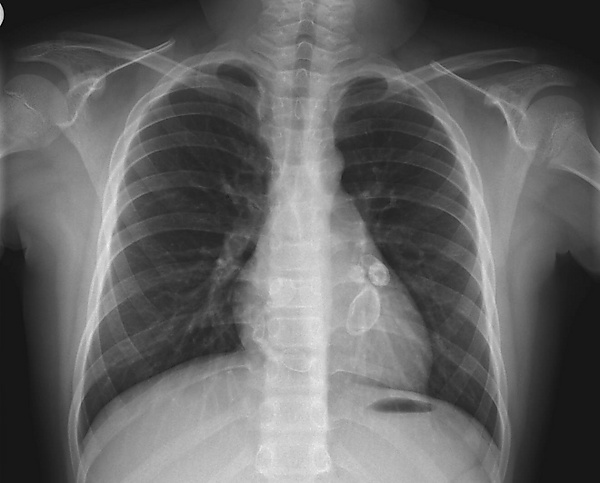

Для синдрома Кавасаки характерно вовлечение в патологический процесс сердечно-сосудистой системы. Могут поражаться перикард, миокард, проводящая система сердца, эндокард, клапанный аппарат. Кроме того, для данного синдрома характерно поражение коронарных артерий с развитием аневризм, что является особенностью данного васкулита[5].